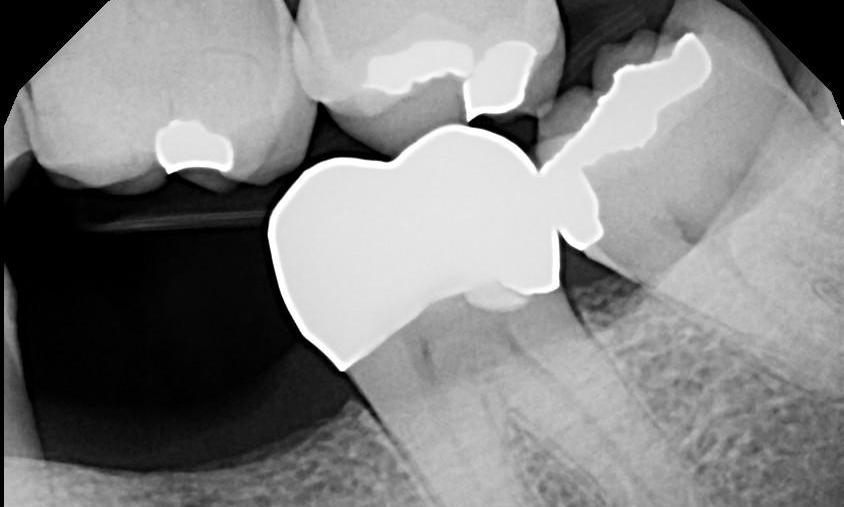

Here is a patient’s molar with a large silver filling with multiple cracks throughout. The patient was beginning to have sensitivity when chewing food. We suspected there was a crack in the tooth. Because the filling was showing such wear and because the tooth was becoming sensitive, we recommended a crown (cap). When we removed the old silver filling, we noticed the crack (noted by the red arrows). Given enough time this crack would have propagated (similar to a crack in a windshield) and the tooth would have broken in half down to the nerve. After placing the tooth-colored crown, this tooth is very well protected and the crack will not progress. The crown not only protects the tooth but it looks way better than the previous silver filling. The X-Ray also shows the crown is fully “seated.” Please visit our FAQ section on the upper right to see why a seated crown is crucial to long-term success of a crown.